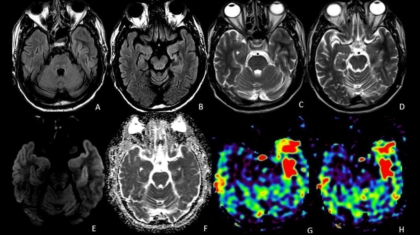

An elderly male, known diabetic with one episode of seizure. What is the diagnosis?